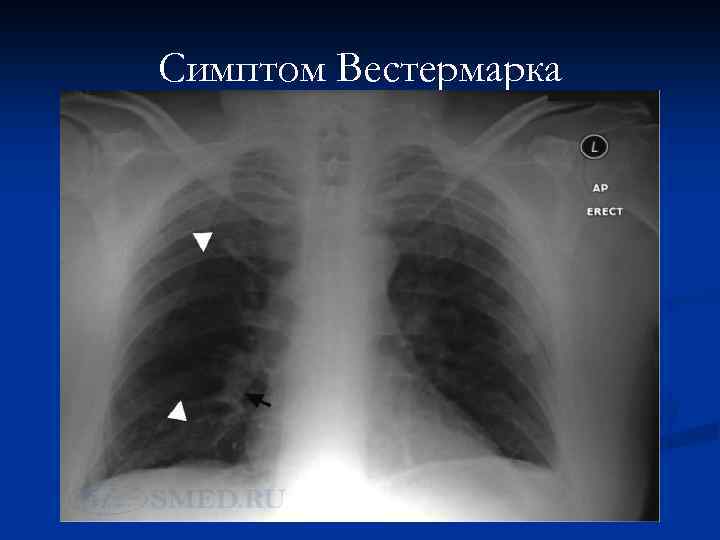

Малоспецифичные рентгенологические признаки ТЭЛА: -высокое стояние купола диафрагмы на стороне поражения; -инфильтрация легочной ткани (спустя 12– 36 ч от начала заболевания); -выбухание конуса легочной артерии; увеличение правых отделов сердца; -расширение верхней полой вены и др. - симптом Вестермарка – обеднение легочного рисунка в области поражения, что свидетельствует о массивной эмболии легочной артерии. - классические признаки инфаркта легкого (редко)– треугольную тень в легочном поле, основанием обращенную к плевре

Симптом Вестермарка